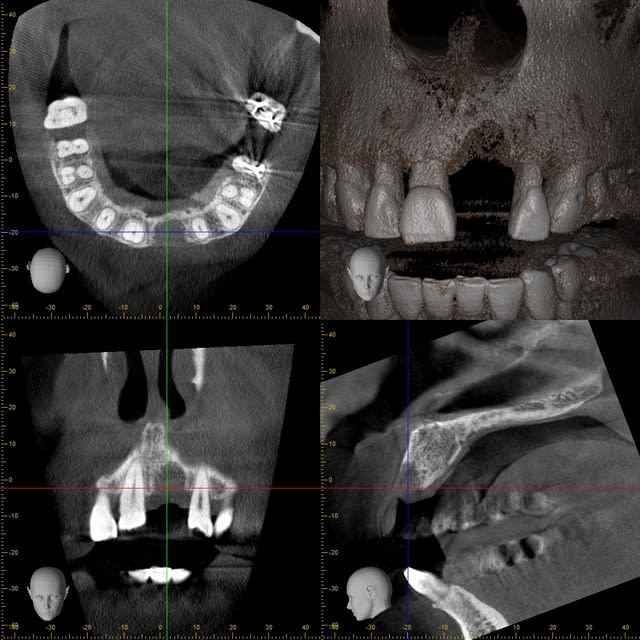

je viens de tomber sur une clé usb avec quelques images...

Guenfra i5kyps - Eugenol

Xyzview 20140607 112446 ida9qe - Eugenol

Xyzview 20140703 133108 osyuum - Eugenol

Volumerenderer 20140703 1331 wcokhm - Eugenol

Xyzview 20140619 122545 wt8h7c - Eugenol